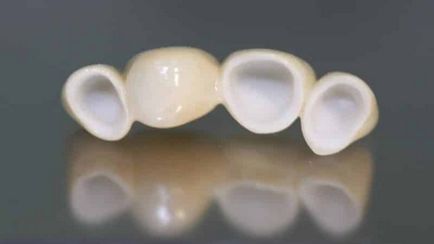

Hiányában a fog vagy több fog, nem egy mondat ma. Telepítés a korona, a másik protézis. A korona lehet állítani, hogy egy adott fogpótlást vagy felszerelésére másik protézist, amelyet arra terveztek, hogy reprodukálja a számot. Ez nem csak azért szükséges, hogy megőrizzék az esztétikus megjelenés, hanem a megfelelő elosztását rágóizmok funkció, különben az egyenleg zavar, fenyegető lazítás és az elmozdulás a szomszédos fogak.

Hogyan tegyük egy korona a fog egy fénykép nehéz megérteni, általában a végeredményt, és előzi meg több szakaszból áll, minden kezdődik a vizsgálat és konzultáció.

Az anyagválasztás függ a protézis, amely esetekben a koronát hozott egy foga. A fogorvos ajánlhatja a sajátos szerinti ötvözet fizikai, klinikai indikációk. Az elülső fogak előnyös a kerámia, mert átveszi a színét a zománc.